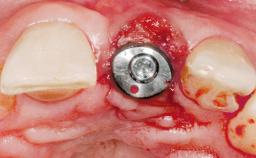

A 30-year-old female patient had lost tooth 21 and was referred to our clinic for consultation and treatment. Due to advanced apical infection, tooth 21 had been extracted two months earlier at another clinic and an acrylic-resin tooth had been bonded to the adjacent teeth. The patient desired implant treatment to avoid any damage to the adjacent natural teeth. While the patient had no history of any systemic disorder, she was a heavy smoker and exhibited medium to advanced periodontitis in the entire jaw. After the initial treatment to achieve a pocket probing depth of less than 4 mm and no bleeding on probing, a decrease in the height of the papillae mesial and distal to the extraction site and overall gingival recession were observed.

Type of Implants One-Piece|Reduced-Diameter

Attachment One-Piece|Reduced-Diameter

Soft Tissue Grafting Simultaneous